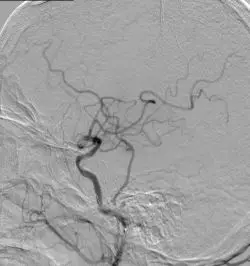

颈内动脉DSA提示颅内存在三处病变血管:大脑中动脉上干闭塞,下干的起始段局部有血栓形成以及一支M2段分支闭塞。

下干取栓后DSA可见下干开通,M2分支以及大脑中动脉上干部分开通。

使用4-20 Solitaire 支架进行MCA上干取栓。 取栓后DSA提示上干完全再通,M2远端分支仍闭塞。

使用4-20 Solitaire 支架进行M2远端分支取栓。 取栓后DSA提示三支病变血管均完全开通。